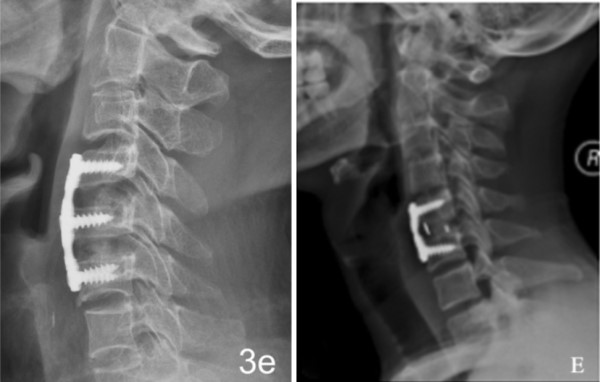

注册证名称:医用纳米羟基磷灰石/聚酰胺66复合骨充填材料

1.优异的生物相容性和生物活性

2.力学性能与自体骨匹配

3.弹性模量接近自体骨,有效减少应力遮挡